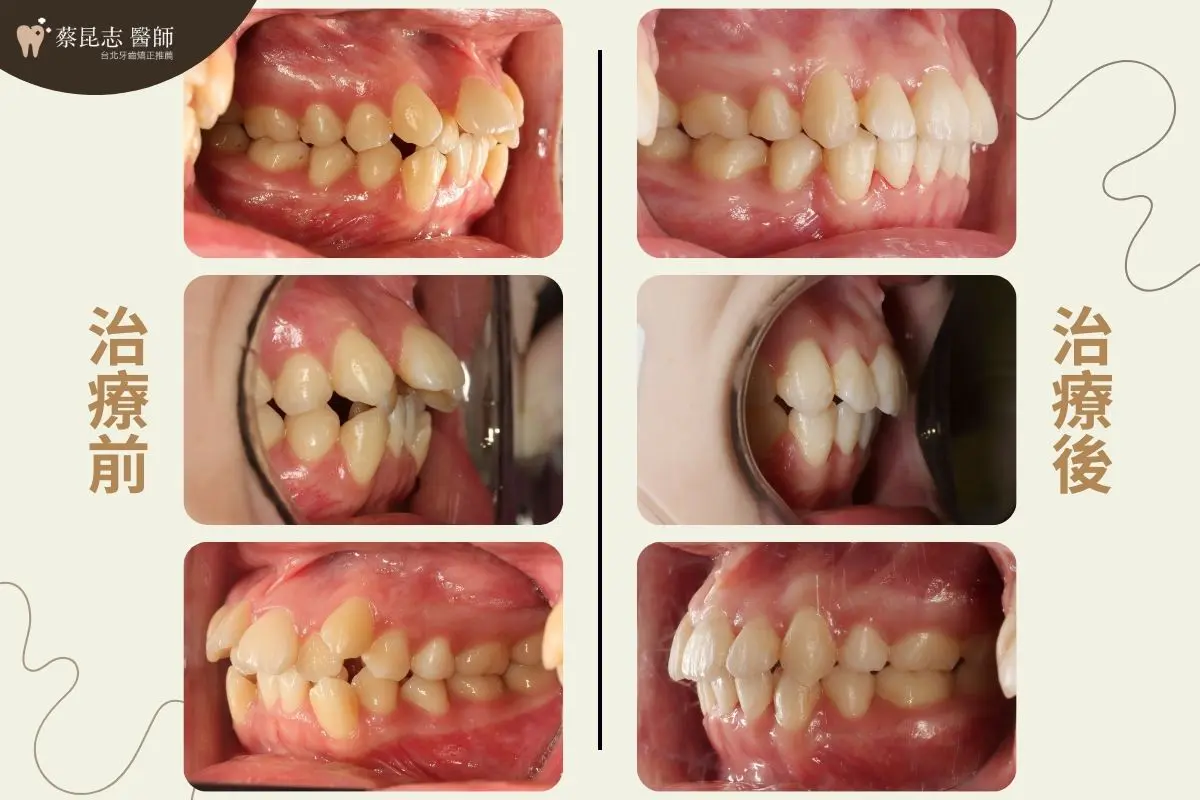

治療計畫是拔除上、下顎左右兩側各一顆第一小臼齒,讓嚴重擁擠上下顎前牙,有空間可以排列整齊。

將上、下顎前牙後縮,恢復上下顎前牙正常咬合,並改善側臉輪廓上唇過於外凸的外觀,凸顯側臉下巴輪廓。